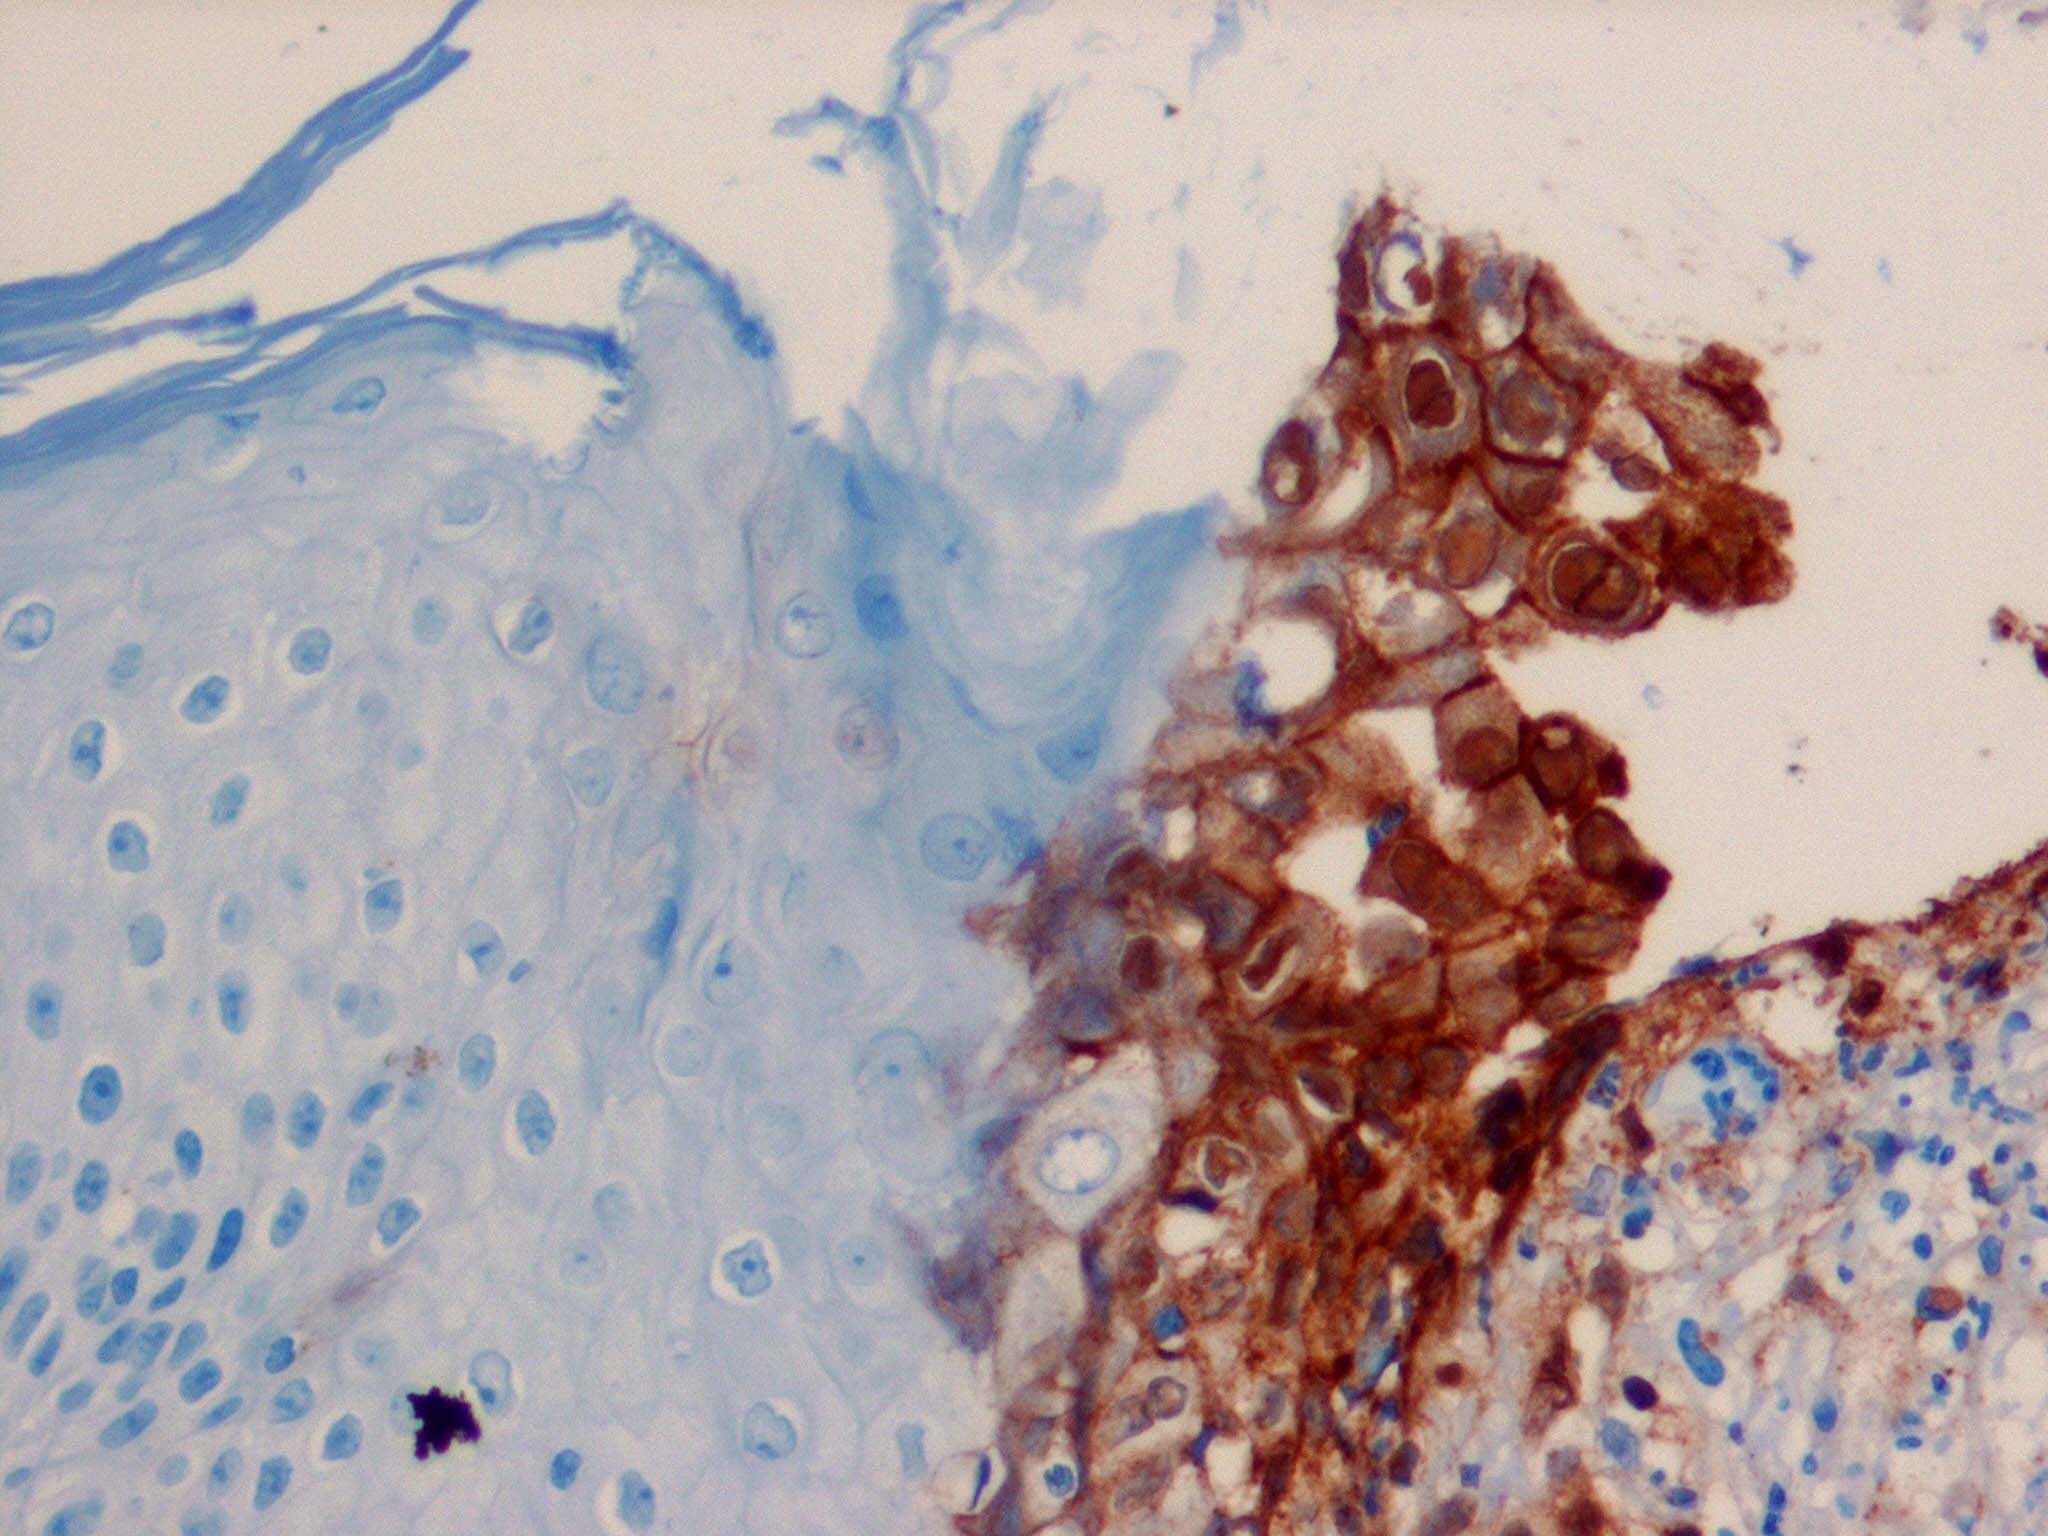

Herpes simplex = العقبول البسيط